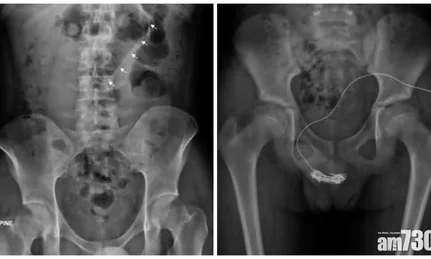

男童及母親曾嘗試取出電線但不成功,母親於是帶男童到醫院求助,照X光片檢查,顯示陰莖尿道上纏有的電線長達20厘米,當中未包括糾纏的部分,無法以牽引方式取出電線,最終決定開刀切開陰莖中段的尿道,取走電線。男童術後兩天出院,需「孭尿袋」兩周才恢復。不過醫生指,需幫男童進行重建尿道手術,他日後或會出現尿道收窄等後遺症。

而另一宗個案發生在去年5月,一名15歲男童停課期間上網尋找「偏方」,解決便秘問題,強行把洗頭水樽塞進肛門,翌日到急症室求醫,當時並未覺痛,檢查發現洗頭水樽被塞至橫結腸附近,男童留院一晚後自行排出洗頭水樽。醫護人員亦有教他解決便秘的正確方法。